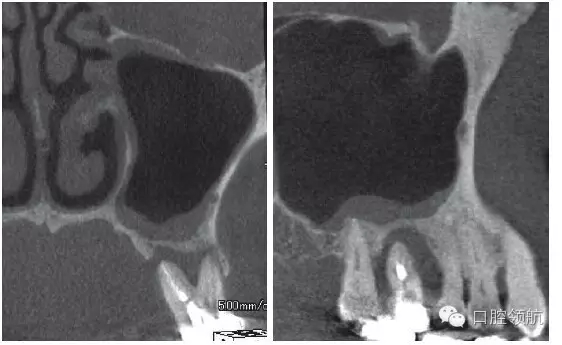

患者,78歲,男性 ,因6 牙齦腫脹來院,檢查見牙根周圍因牙槽骨缺損表現(xiàn)為透過影像(圖1)。在制訂治療計劃時,對于因重度牙周炎、慢性根尖周炎、牙根折斷等原因?qū)е碌难例X缺失需要行上頜竇底提升術(shù)的病例,不能單純考慮缺牙區(qū),要同時考慮鄰牙狀態(tài),并用CBCT確認上頜竇底黏膜是否有增厚,這是非常重要的。該病例,根據(jù)CBCT能夠觀察到上頜竇底黏膜增厚,拔牙即刻植入感染幾率較高。計劃拔牙后4~8周,拔牙窩牙齦上皮愈合但拔牙窩未消失時(拔牙后早期植入)植入種植體(圖2)。

圖1 CBCT影像確認是由6 引起的上頜竇底黏膜增厚。